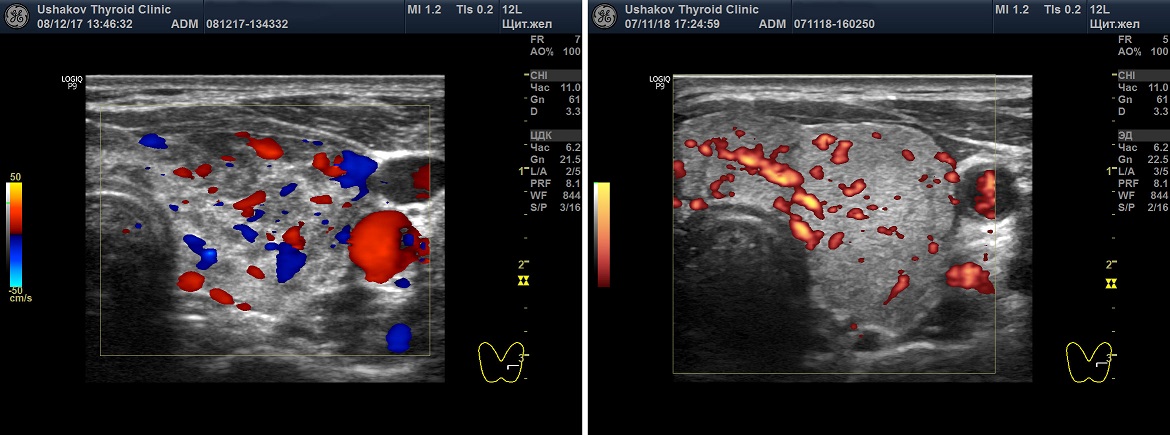

Рисунок. 7. Неупорядоченный кровоток узлов щитовидной железы.

Клиника щитовидной железы доктора А.В. Ушакова ввела такой признак оценки кровотока как его «упорядоченность». Под упорядоченностью кровотока узла понимается расположение сосудов в соответствии с естественным сегментарным устройством ткани узла. Упорядоченность кровотока узлов может быть в разной степени выражена. Беспорядочный кровоток (т.е. независимо от сегментов) относится к важному признаку злокачественности ткани узла. Такое беспорядочное расположение сосудов возникает при неравномерном и несегментированном прорастании сосудов вместе с образованием раковой ткани.